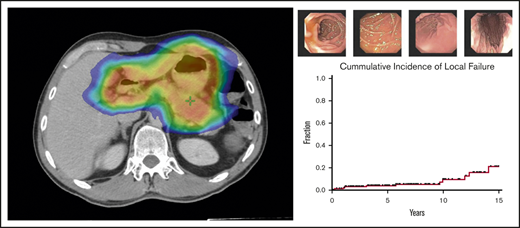

Local failures

Over a median follow-up of 6.2 years from the end of RT (range, 19.7 months-23 years), 12 of 166 patients (7%) treated for early-stage disease experienced local failures. Five-year and 10-year local failure rates, using death as a competing risk, were 3.9% and 8.3%, respectively (Figure 4). Median time to local disease failure was 4.4 years (range, 3 months-14 years). One patient who developed DLBCL of the stomach 1 year after RT was treated with cyclophosphamide, doxorubicin, vincristine, and prednisone (CHOP) chemotherapy and died of disease a year later. The remaining local relapses were associated with refractory GML on EGD biopsy. Salvage therapies included rituximab, additional radiotherapy, and rituximab (R)-CHOP.

Local and distant disease failures. Cumulative incidence of local and distant failures for patients treated for early-stage GML (N = 166), using death as a competing risk. Five-year and 10-year local failure rates were 3.9% and 8.3%, respectively, whereas 5-year and 10-year distant failure rates were 6.9% and 11%, respectively.

Distant failures

Among patients treated for early-stage disease, 16 of 166 patients (10%) developed distant sites of disease. Five-year and 10-year distant failure rates were 6.9% and 11%, respectively (Figure 4). Median time to distant disease failure was 4.7 years (range, 11 months-15 years). Four of these 16 patients (25%) presented with transformation to DLBCL at distant sites, including colon and retroperitoneum (2 patients each). Median time to DLBCL transformation was 3.6 years (range, 11 months-4.7 years). Despite distant relapse, all 16 patients were found to be free of local disease on posttreatment EGD biopsy. Subsequent treatments included chemotherapy, additional radiation, rituximab monotherapy, salvage surgery, and observation.